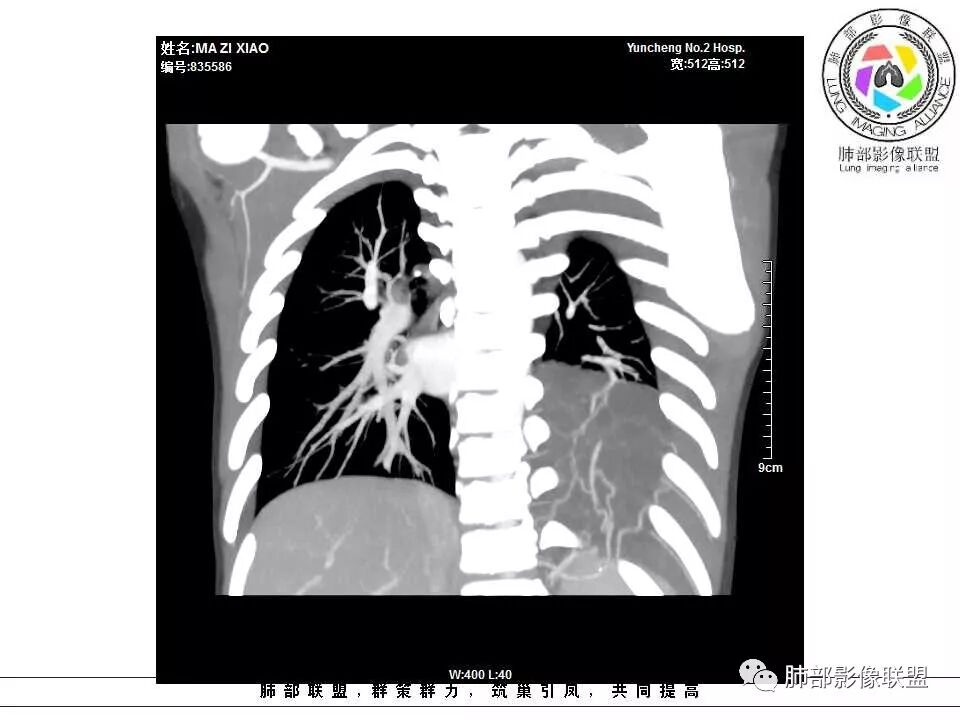

电话随访,患者在西安某医院手术,为肺隔离症,供血两支动脉,均来自腹主动脉,引流入肺静脉。

一、隔离症的血管

1.有体循环供血动脉

2.并无伴行静脉,回流到纵隔的血管不容易见到

3.相应流量的静脉,在隔离症周围通常仅有肺静脉

4.供血动脉形态有改变,常有扩张及退变